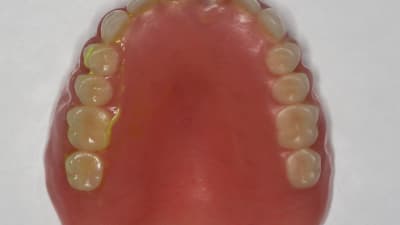

Clinical Briefs CAD | CAM Prosthodontics Fabricating New Dentures From Existing Ones By Rami Ammoun, DDS September 01, 2021 6 min read